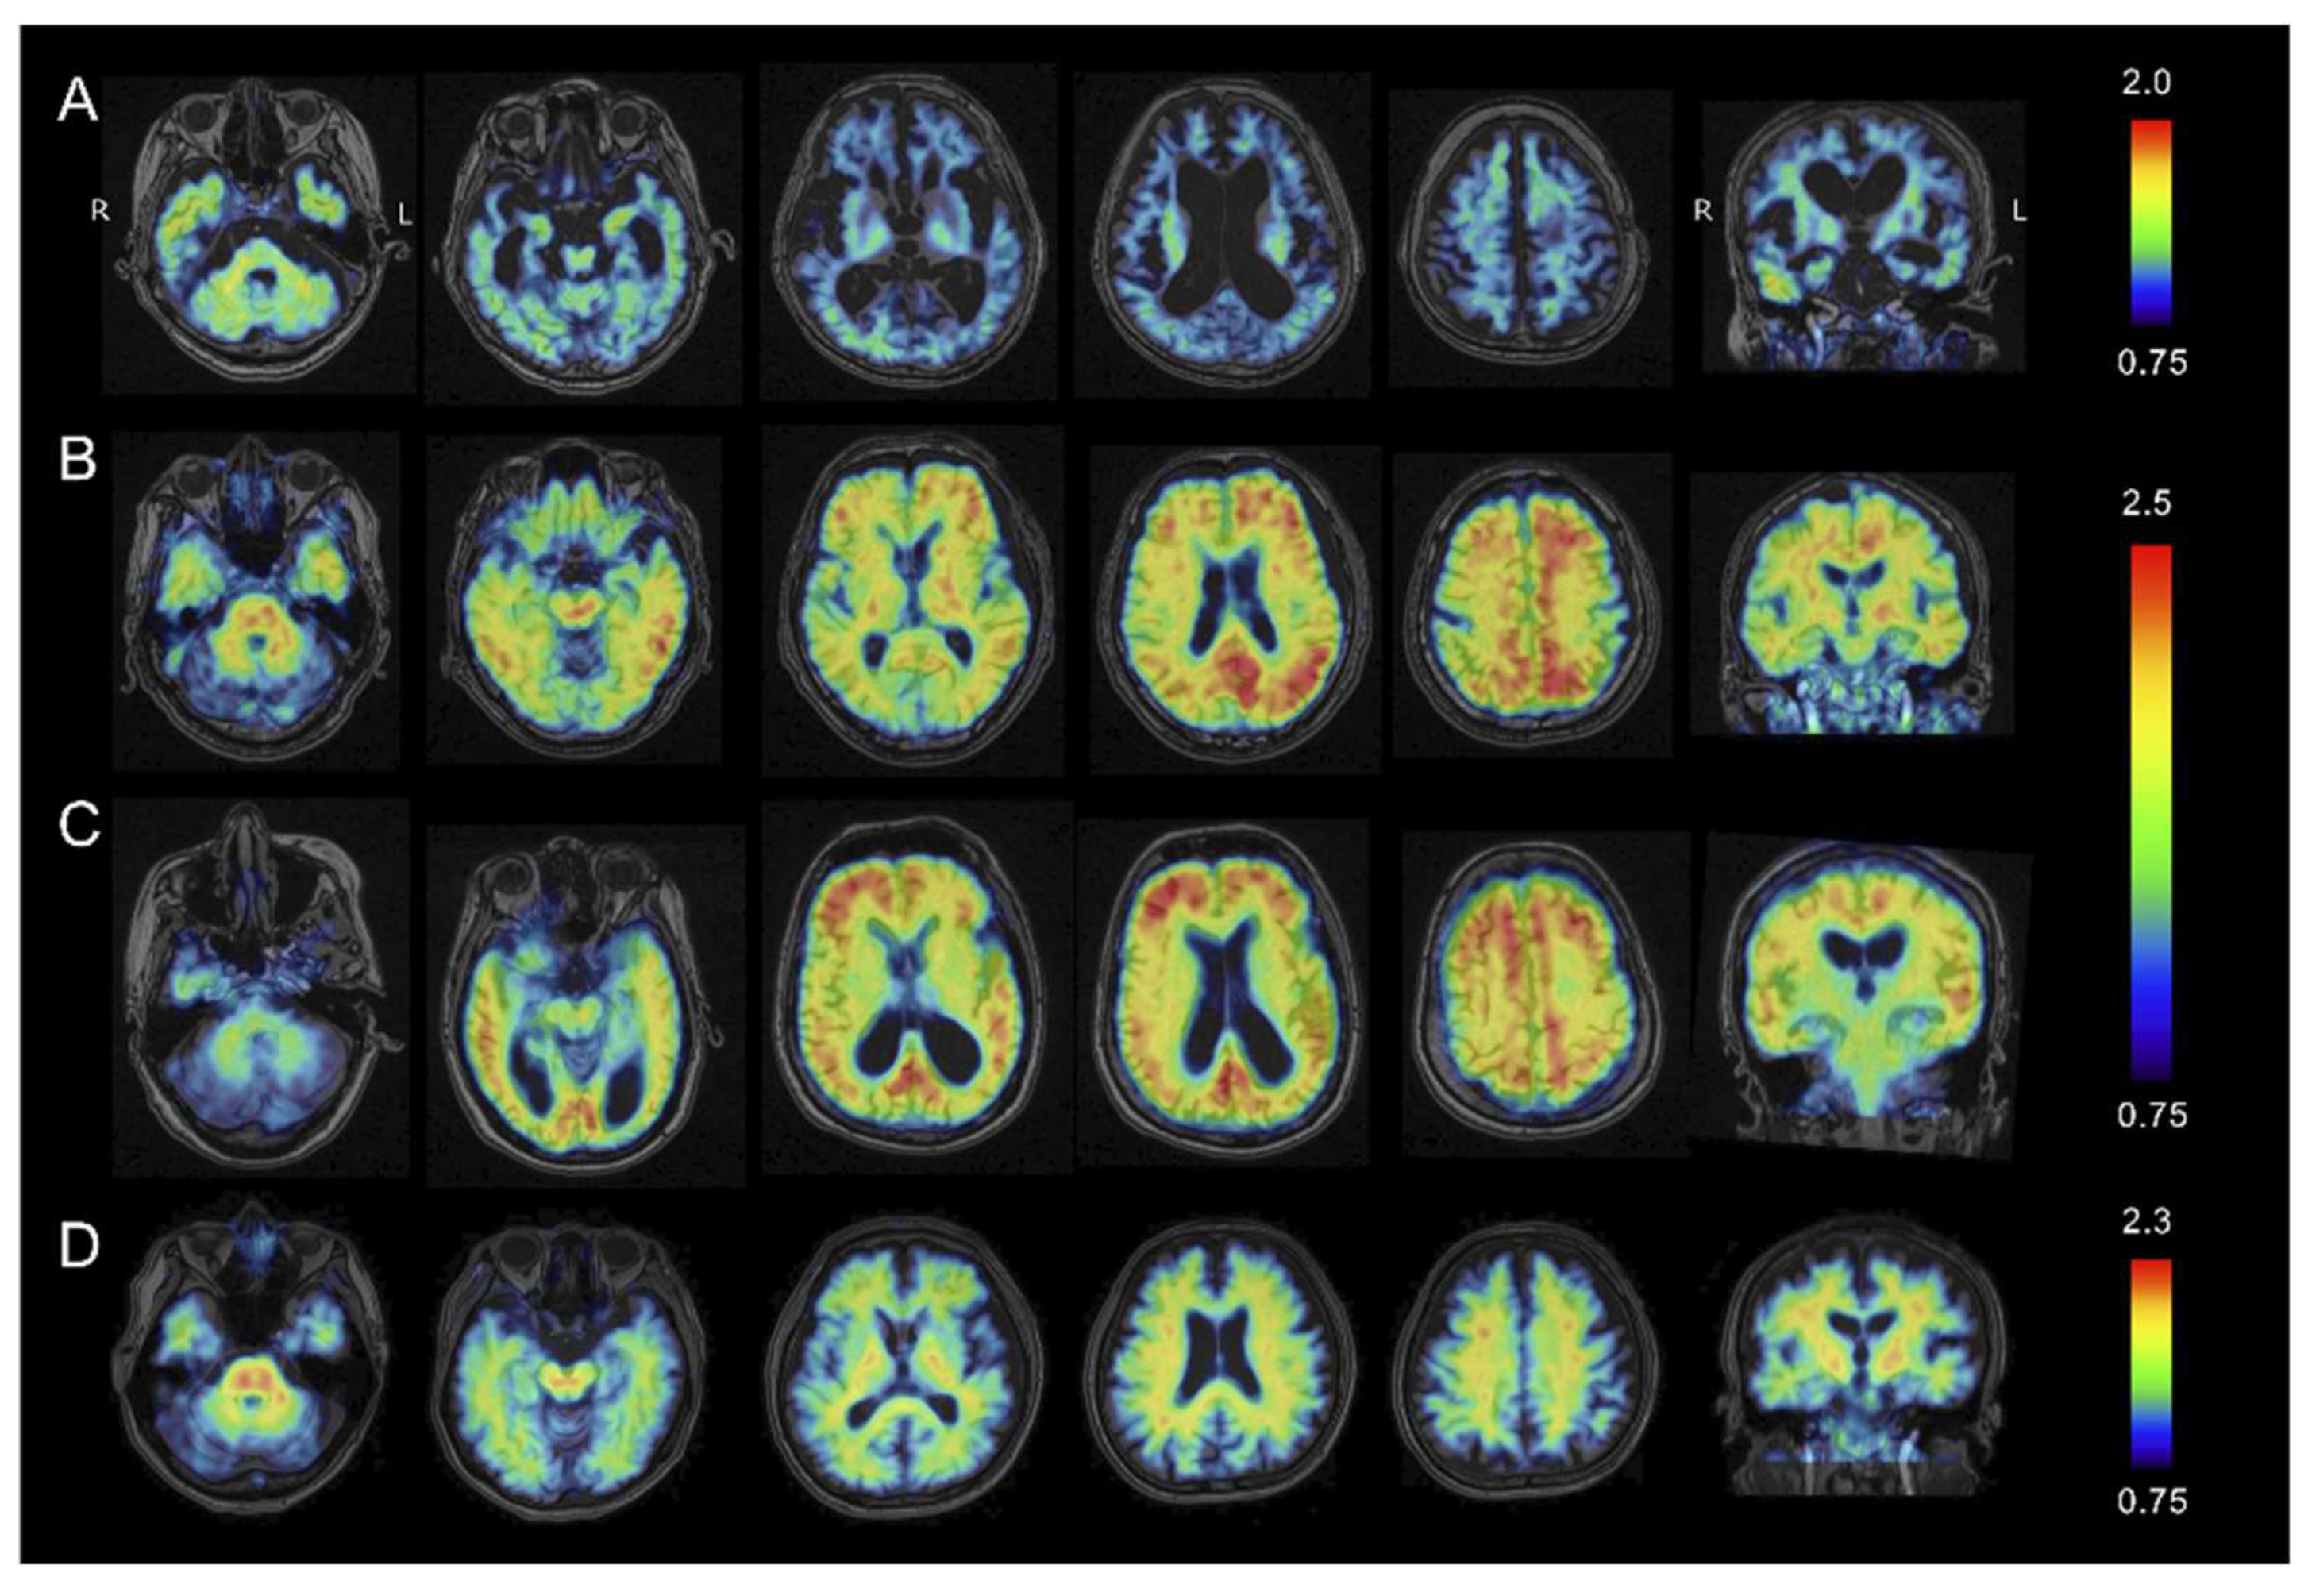

2.3. Tau PET Imaging